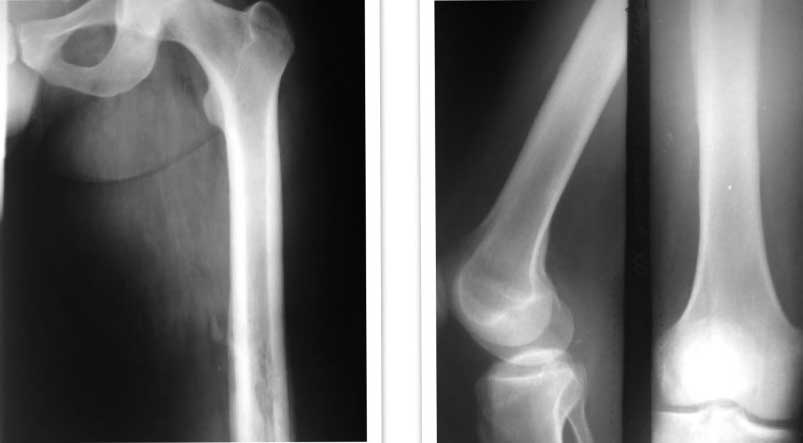

[Ortho] остеомиелит бедра

Имя     : femur.jpg